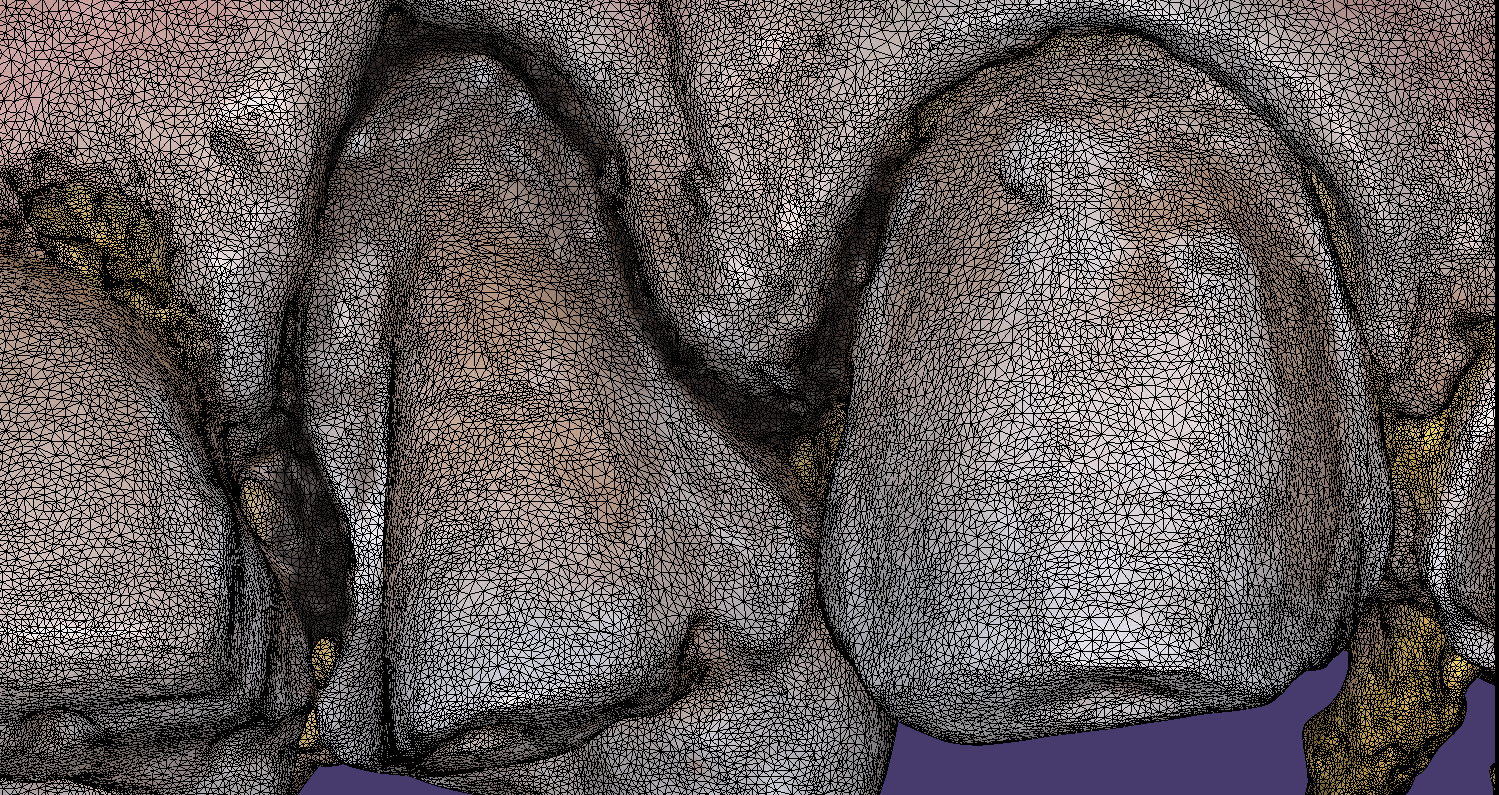

May 29, 2019A friendly reminder- this case was table top scanned with a desktop scanner so don’t get distracted, but be aware that for oral appliances, particularly for apnea treatment or bruxism, […]